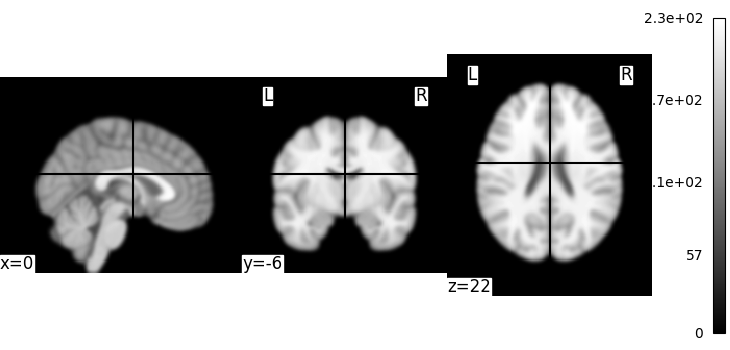

We could also pass it to the smoothing function

<nilearn.plotting.displays._slicers.OrthoSlicer object at 0x7f1ee830ef80>